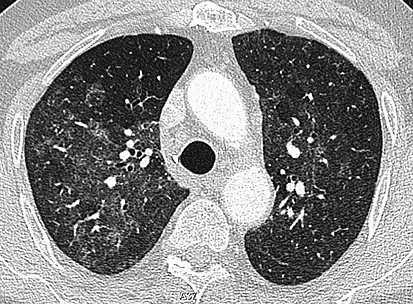

High-Resolution CT image in a patient with Pneumocystis pneumonia infection showing ground-glass opacities.

Inflammation and fibrosis can also cause diffuse GGOs. Pneumocystis pneumonia, an infection typically seen in immunocompromised (e.g. patients with AIDS) or immunosuppressed individuals, is a classic cause of diffuse GGOs. Many viral pneumonias and idiopathic interstitial pneumonias can also lead to a diffuse GGO pattern. Radiation pneumonitis, a side effect of pulmonary radiation therapy, can lead to pulmonary fibrosis and diffuse GGOs.[6]